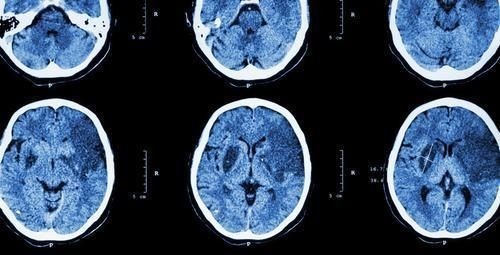

脑血管|睡觉出现4个异常,说明脑血管堵了,做好4个字,清血脂通血管

脑梗的死亡率高达70%,已经成为我国一大致死原因,而在经过了先进治疗的一部分人中,也可能留下偏瘫的后遗症。因此,积极预防脑梗至关重要。

睡觉时出现4个异常,说明脑血管堵了,尽早检查1、头痛晚上人体的活动减少,血液粘稠度更高,更容易形成血栓,堵塞血管。一旦脑血管堵塞,就会出现持续性的头痛,这种头痛可能导致人难以再入睡。2、手脚麻木睡觉时频繁出现手脚麻木,尤其是单侧性的,要警惕。当脑血管堵塞,脑供血不足时,会引起大脑皮层脊髓通路,处于肢体末端的手脚表现更加明显。患者还可能会有突然拿不住东西、手持物体突然掉落等症状。3、单侧流口水经常睡觉时不自觉的流口水,要警惕脑血管堵塞。大脑缺血缺氧时,会使双侧的皮质脑干束受到影响,导致舌下功能紊乱,使患者出现单侧流口水、嘴歪眼斜、眼角闭合不严等症。当动脉硬化及脑缺血缺氧严重时,患者还会出现频繁打哈欠的现象,要及时就医。